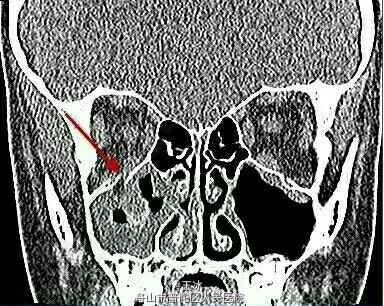

眼部检查:患者近视力1.0,无视野缺损。第一眼位如图1所示。右眼上视有-4的眼球上转不足(图2),下视有-2的下转不足。左眼运动正常。双眼水平运动正常。右眼第一眼位时眼压为13mmHg,上视时眼压增加至23mmHg。左眼眼压为12mmHg。瞳孔正常,双眼附属器以及前后节正常。眼球无震颤。颌面部CT(图3)显示右眼眶底轻微骨折。

诊断:眼眶活板门样骨折致下直肌嵌顿。 手术:紧急前眶探查手术 术中发现活板门样骨折伴下直肌和眼眶脂肪嵌顿。释放嵌顿组织,骨折处植入人造眼眶底板。眼球运动恢复正常。

随访:术后 7 周内,患者恶心症状消失,眼球运动障碍和复视现象消失。 讨论: 儿童尤其容易发生此型骨折。儿童骨质相对具有弹性,骨折后会产生反弹,使覆盖于上方的肌肉或者相邻的 组织嵌入骨折缝(图 3)。这种肌肉嵌顿可以导致特征性的眼球运动障碍。本例患者恶心呕吐的症状提示眼心反射的可能性。 眼眶的钝挫伤可导致开放性眼球损伤,但是,该患者眼附属器、瞳孔、眼内压以及前后节都正常,所以不考虑开放性眼球损伤。 尽管眼外伤可导致球后出血,出现复视与恶心的症状。此患者眼球不突出,视力正常,眼压正常,且眼周无瘀血、瘀斑,暂不考虑球后出血的可能性。 患者脑外伤后偶发复视,多数由于辐辏不足或者眼球平稳跟踪运动功能损伤,伴随恶心与呕吐症状。但是该患者精神状态正常,垂直性眼动不足,颌面部 CT 显示眼眶底骨折伴肌肉嵌顿。 外伤性滑车神经麻痹会引起受累眼下转、内转不足,常伴有下斜肌亢进,内转时会有眼球上漂。患者眼球垂直性运动障碍以上转不足更为明显,而水平运动则正常。